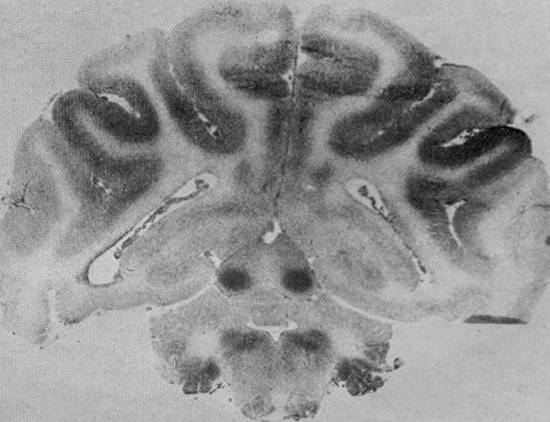

Figure xx -  Autoradiograph showing blood flow in the brain of a newborn monkey.  The

greatest blood flow is to the inferior colliculi in the midbrain.  High blood flow is also seen in

other subcortical structures and inner sulci of the cerebral cortex (with permission from the

American Medical Association).

Figure xx is an autoradiograph from Myers' article

showing greatest localization of the radiographic tracer

in the inferior colliculi of a newborn monkey [1, p254].